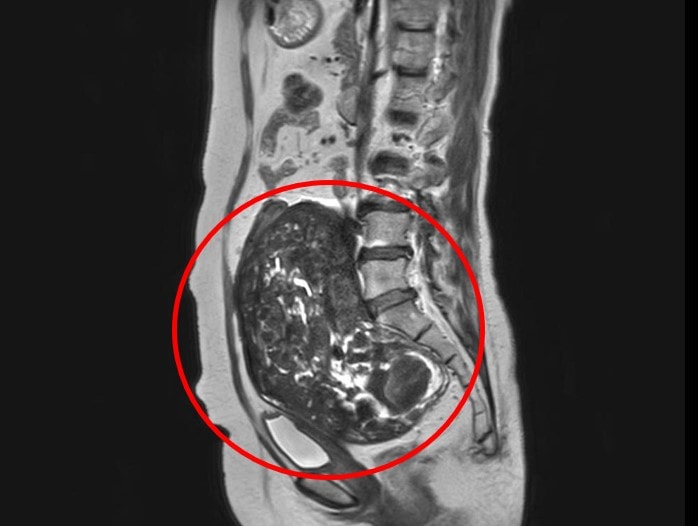

Khối nhân xơ tử cung trong ổ bụng bệnh nhân.

Qua thăm khám và thực hiện các cận lâm sàng, đặc biệt là chụp cộng hưởng từ (MRI) 3.0T tích hợp trí tuệ nhân tạo (AI), các bác sĩ xác định bệnh nhân có khối đa nhân xơ tử cung kích thước lớn đã thoái hóa, bám dính vào bờ trước thân sống thắt lưng cùng và bó mạch chậu phải. Khối u không chỉ phát triển lớn mà còn chèn ép các cơ quan lân cận, tiềm ẩn nhiều nguy cơ nếu không can thiệp kịp thời.

Sau khi hội chẩn, ê kíp bác sĩ quyết định phẫu thuật cắt hoàn toàn tử cung kèm hai phần phụ cho bệnh nhân. Tuy nhiên, trong quá trình phẫu thuật, các bác sĩ gặp không ít khó khăn do khối u kích thước lớn và dính chặt vào nhiều cơ quan. Mặt trước khối u dính vào bàng quang, trong khi mặt sau bám vào đại tràng và trực tràng, khiến việc bóc tách và gỡ dính trở nên phức tạp.

Các bác sĩ phẫu thuật đã phải thực hiện thao tác tỉ mỉ, vừa bóc tách khối u vừa kiểm soát chặt chẽ tình trạng chảy máu để đảm bảo an toàn cho người bệnh. Sau gần 2 giờ phẫu thuật căng thẳng, khối u được lấy ra khỏi cơ thể bệnh nhân với cân nặng 2.100 gram (2,1kg) và mẫu bệnh phẩm sau đó được gửi làm giải phẫu bệnh để xác định bản chất lành tính hay ác tính.